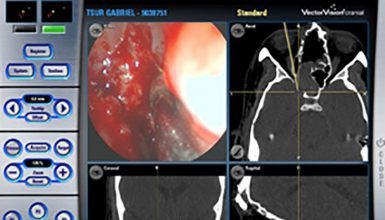

במטרה לפתור קשיים אלו, רתמו מנתחי האף והסינוסים לשרותם אמצעי טכנולוגי חדיש ומתוחכם, המהווה פריצת דרך בהגברת יעילות ובטיחות הניתוחים האנדוסקופיים – מערכת מונחית דימות (Image-guidance system). באמצעות קרני איפרה אדום מאפשרת המערכת למנתח לצפות במיקומו המדוייק של קצה הכלי הניתוחי אותו הוא אוחז על גבי תצוגה תלת-מימדית של CT או MRI אותם ביצע המנותח טרם הניתוח (תמונה מס' 1).

תמונה מס' 1